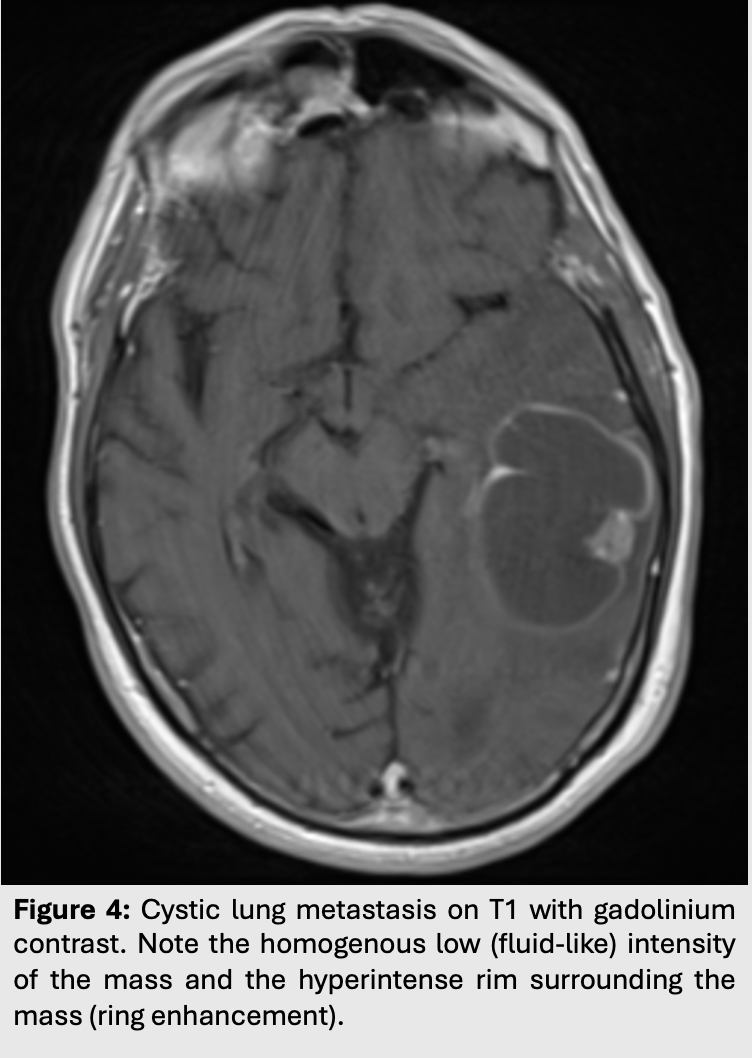

Contrary to cytotoxic edema, vasogenic edema occurs in situations where the blood brain barriers is disrupted.

Edema is extracellular and usually results from fluid leakage out the capillaries into the surrounding white matter.

This shows up as edema without diffusion restriction.

As such, vasogenic edema will appear hyperintense on T2/FLAIR but attenuated (hypointense) on DWI.

Vasogenic edema can be caused by many pathologies. Most commonly, it can be found surrounding intra-axial tumors, cerebral abscesses or even around maturing hemorrhages.

Figure 4: Cystic lung metastasis on T1 with gadolinium contrast. Note the homogenous low (fluid-like) intensity of the mass and the hyperintense rim surrounding the mass (ring enhancement).